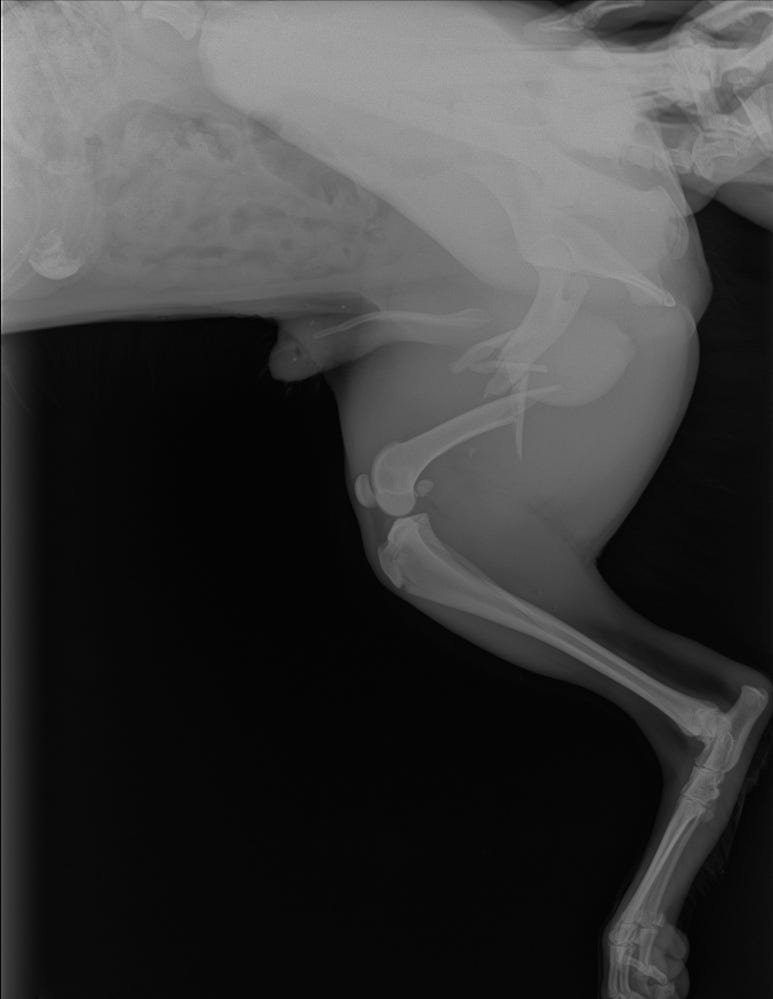

수의사 선생님이 보시더니 골절이 아니고 그냥 상처만 나서 피만 좀 나는 거였으면 좋겠다고.... 엑스레이를 찍어봐야 정확히 알 수 있다고 하셔서 엑스레이와 초음파를 찍었습니다.

결과는..... 너무 슬프게도 골절이었습니다. 단순골절도 아닌 복합골절... 조각조각나서 일반 병원에서는 치료할 수 없을 거라고..대학병원에서나 치료할 수 있다고 .. 금액은 최소 700만원 이상일 거라더군요.

그리고 초음파로는 확인할 수 없지만 요도를 다쳤을수도 있다고

소변을 못보면 그것도 수술을 해줘야 살 수 있다고 하더라구요